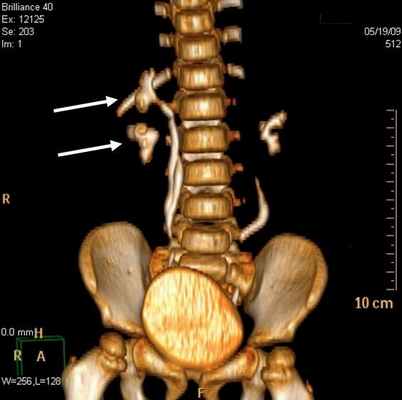

Дополнительные диагностические возможности открываются при реконструкции полученного изображения с применением тонких реконструируемых срезов (1,25 мм), а также построения мультипланарных реконструкций. При этом изменение со стороны мочеточника характеризовалось расширением (62,2%) и деформированием (29,7%) органа (рис 2.).

Во всех наблюдениях устья мочеточников открывались в мочевой пузырь. В отличие от экскреторной урографии на МСКТ четко определяются изменения со стороны почек и мочеточника, особенно при трехмерной реконструкции.

Стеноз устья мочеточника на МСКТ выявлен в 29 (78,4%) наблюдениях (рис 4). Данная патология у 17 детей была с обеих сторон, а 3 наблюдениях этот порок сочетался с уретероцеле и эктопией устьев мочеточника.

Рис 4. Стеноз устья мочеточника. Трехмерная реконструкция. Больной К., 6 лет. Деформирование мочеточников и сужение устья мочеточников